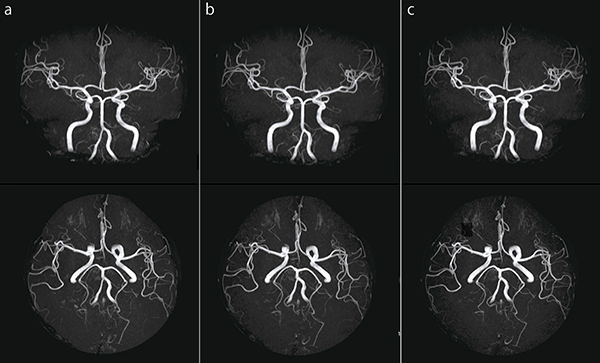

●頭部MRA

図5 aは,IP-RAPIDを使用していない画像です。それに対して図5 bは,IP-RAPIDを使用している画像です。MRAでのIP-RAPIDはk-spaceをCircularで充填するため,RAPID(IP-Scan)の倍速数が小さくても大きな撮像時間短縮効果が得られます。また,図5 cもIP-RAPIDを使用しており,大幅な撮像時間短縮を目的とする場合,RAPID(IP-Scan)の倍速数を大きくします。RAPID(IP-Scan)の倍速数を上げることは,画像のSNRと空間分解能に影響します。場合によっては,RAPID(IP-Scan)以外のパラメータを調整することも必要です。

図5 頭部MRA *Freq/Phase=周波数エンコード数/位相エンコード数

a:IP-RAPID off, Phase=2.0, Freq/Phase=256×256, scan time=4:48

b:IP-RAPID on, Phase=2.0, IP-Scan=1.3, Total=2.6, Freq/Phase=256×256, scan time=2:55

c:IP-RAPID on, Phase=2.0, IP-Scan=2.0, Total=4.0, Freq/Phase=256×256, scan time=1:55

図9 aは,IP-RAPIDを使用していない画像です。それに対して図9 b,cは,IP-RAPIDを使用している画像です。空間分解能向上を目的とする場合,Freq/Phaseを大きくする必要があります。しかし,その結果,撮像時間の延長やボクセルサイズが小さくなることによるSNRの低下が発生します。IP-RAPIDを活用することで,これらのリスクを低減させ,高い空間分解能を持った画像を得ることができます。

図9 頭部MRA

b:IP-RAPID on, Phase=1.6, IP-Scan=1.1, Total=1.7, Freq/Phase=288×288, scan time=4:48

c:IP-RAPID on, Phase=1.6, IP-Scan=1.2, Total=1.9, Freq/Phase=320×308, scan time=4:48